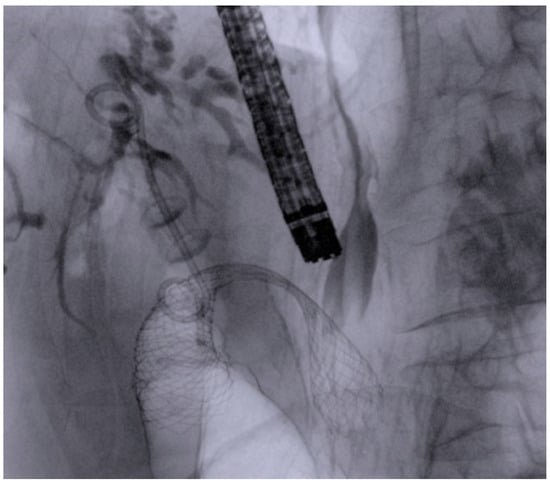

2.1. Procedures